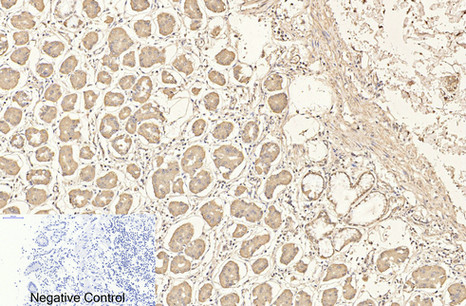

- Immunohistochemistry analysis of paraffin-embedded Human stomach tissue using CD4 antibody.High-pressure and temperature Sodium Citrate pH 6.0 was used for antigen retrieval.Negative control was used by secondary antibody only.